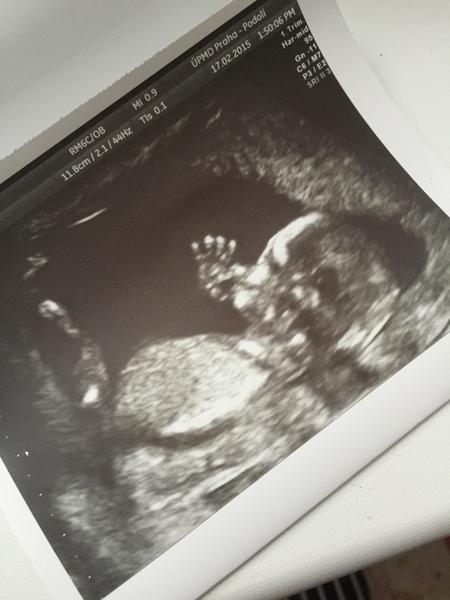

@veronika1810 no jasná holka 🙂 gratuluji 🙂

ja vidím holčičku 🙂 kez bych takovou fotku někdy dostala i ja ☺ ale to uz se a si neprihodi... 🙂 gratuluji ;)

Ahoj holky, dokáže si někdo tipnout? 13.tt, fotka jen z profilu..... Děkuji 🙂